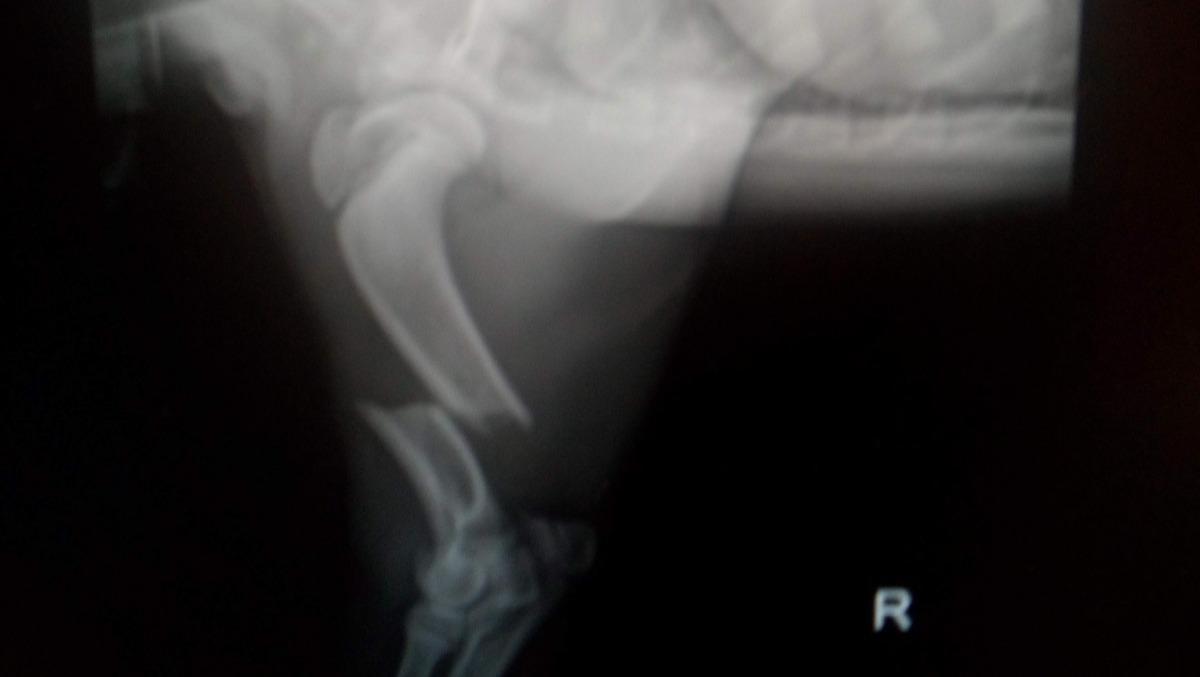

Hi, I am Denis (Catalina's husband) and I would like to ask you to support us in helping our puppy. She was hit by a car in front of our house, and the driver fled the scene. Her name is Eva and due this accident, her right humerus was broken in half (see the radiography below) and needs a surgery to fix this. This initial surgery costs 4000$, leaving aside other follow-up and post-surgery charges.